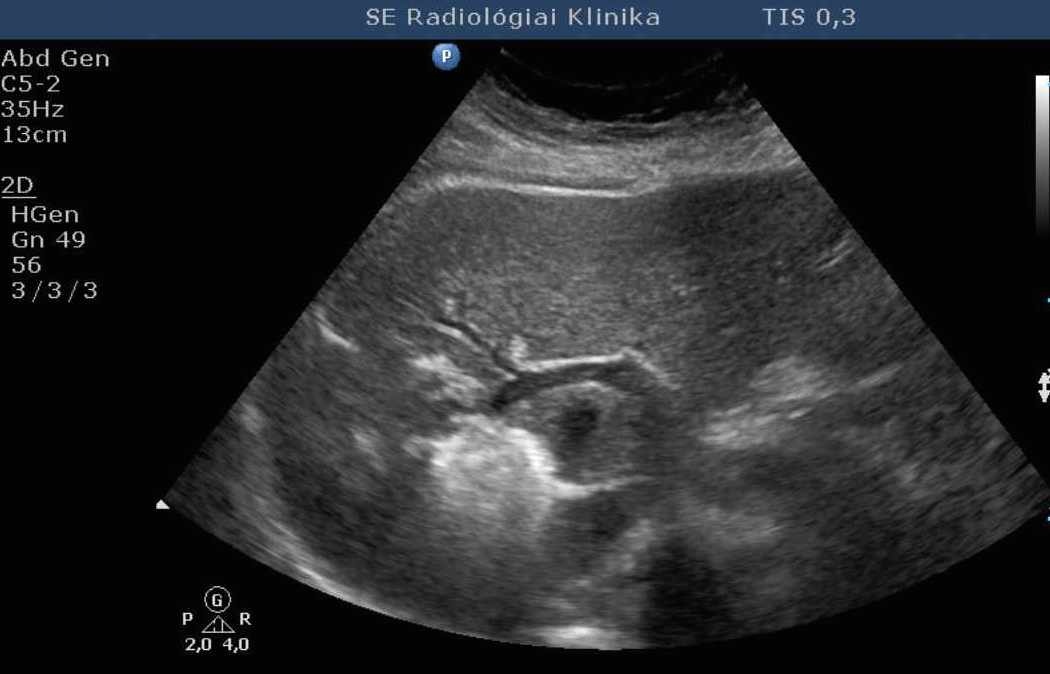

These methods are helpful for the percutaneous treatment or drainage of fluid collections and abscesses (figure 8.).

Image

Figure 8. – UH guided drainage, abdominal wall seroma (drainage of 400 ml)